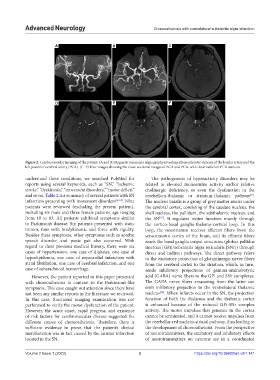

Figure 2. Cerebrovascular imaging of the patient. (A and B) Magnetic resonance angiography revealing atherosclerotic stenosis of the basilar artery and the

left posterior cerebral artery (PCA). (C–F) Four images showing the cross-sectional images of BCA and PCA, with observable left PCA stenosis.